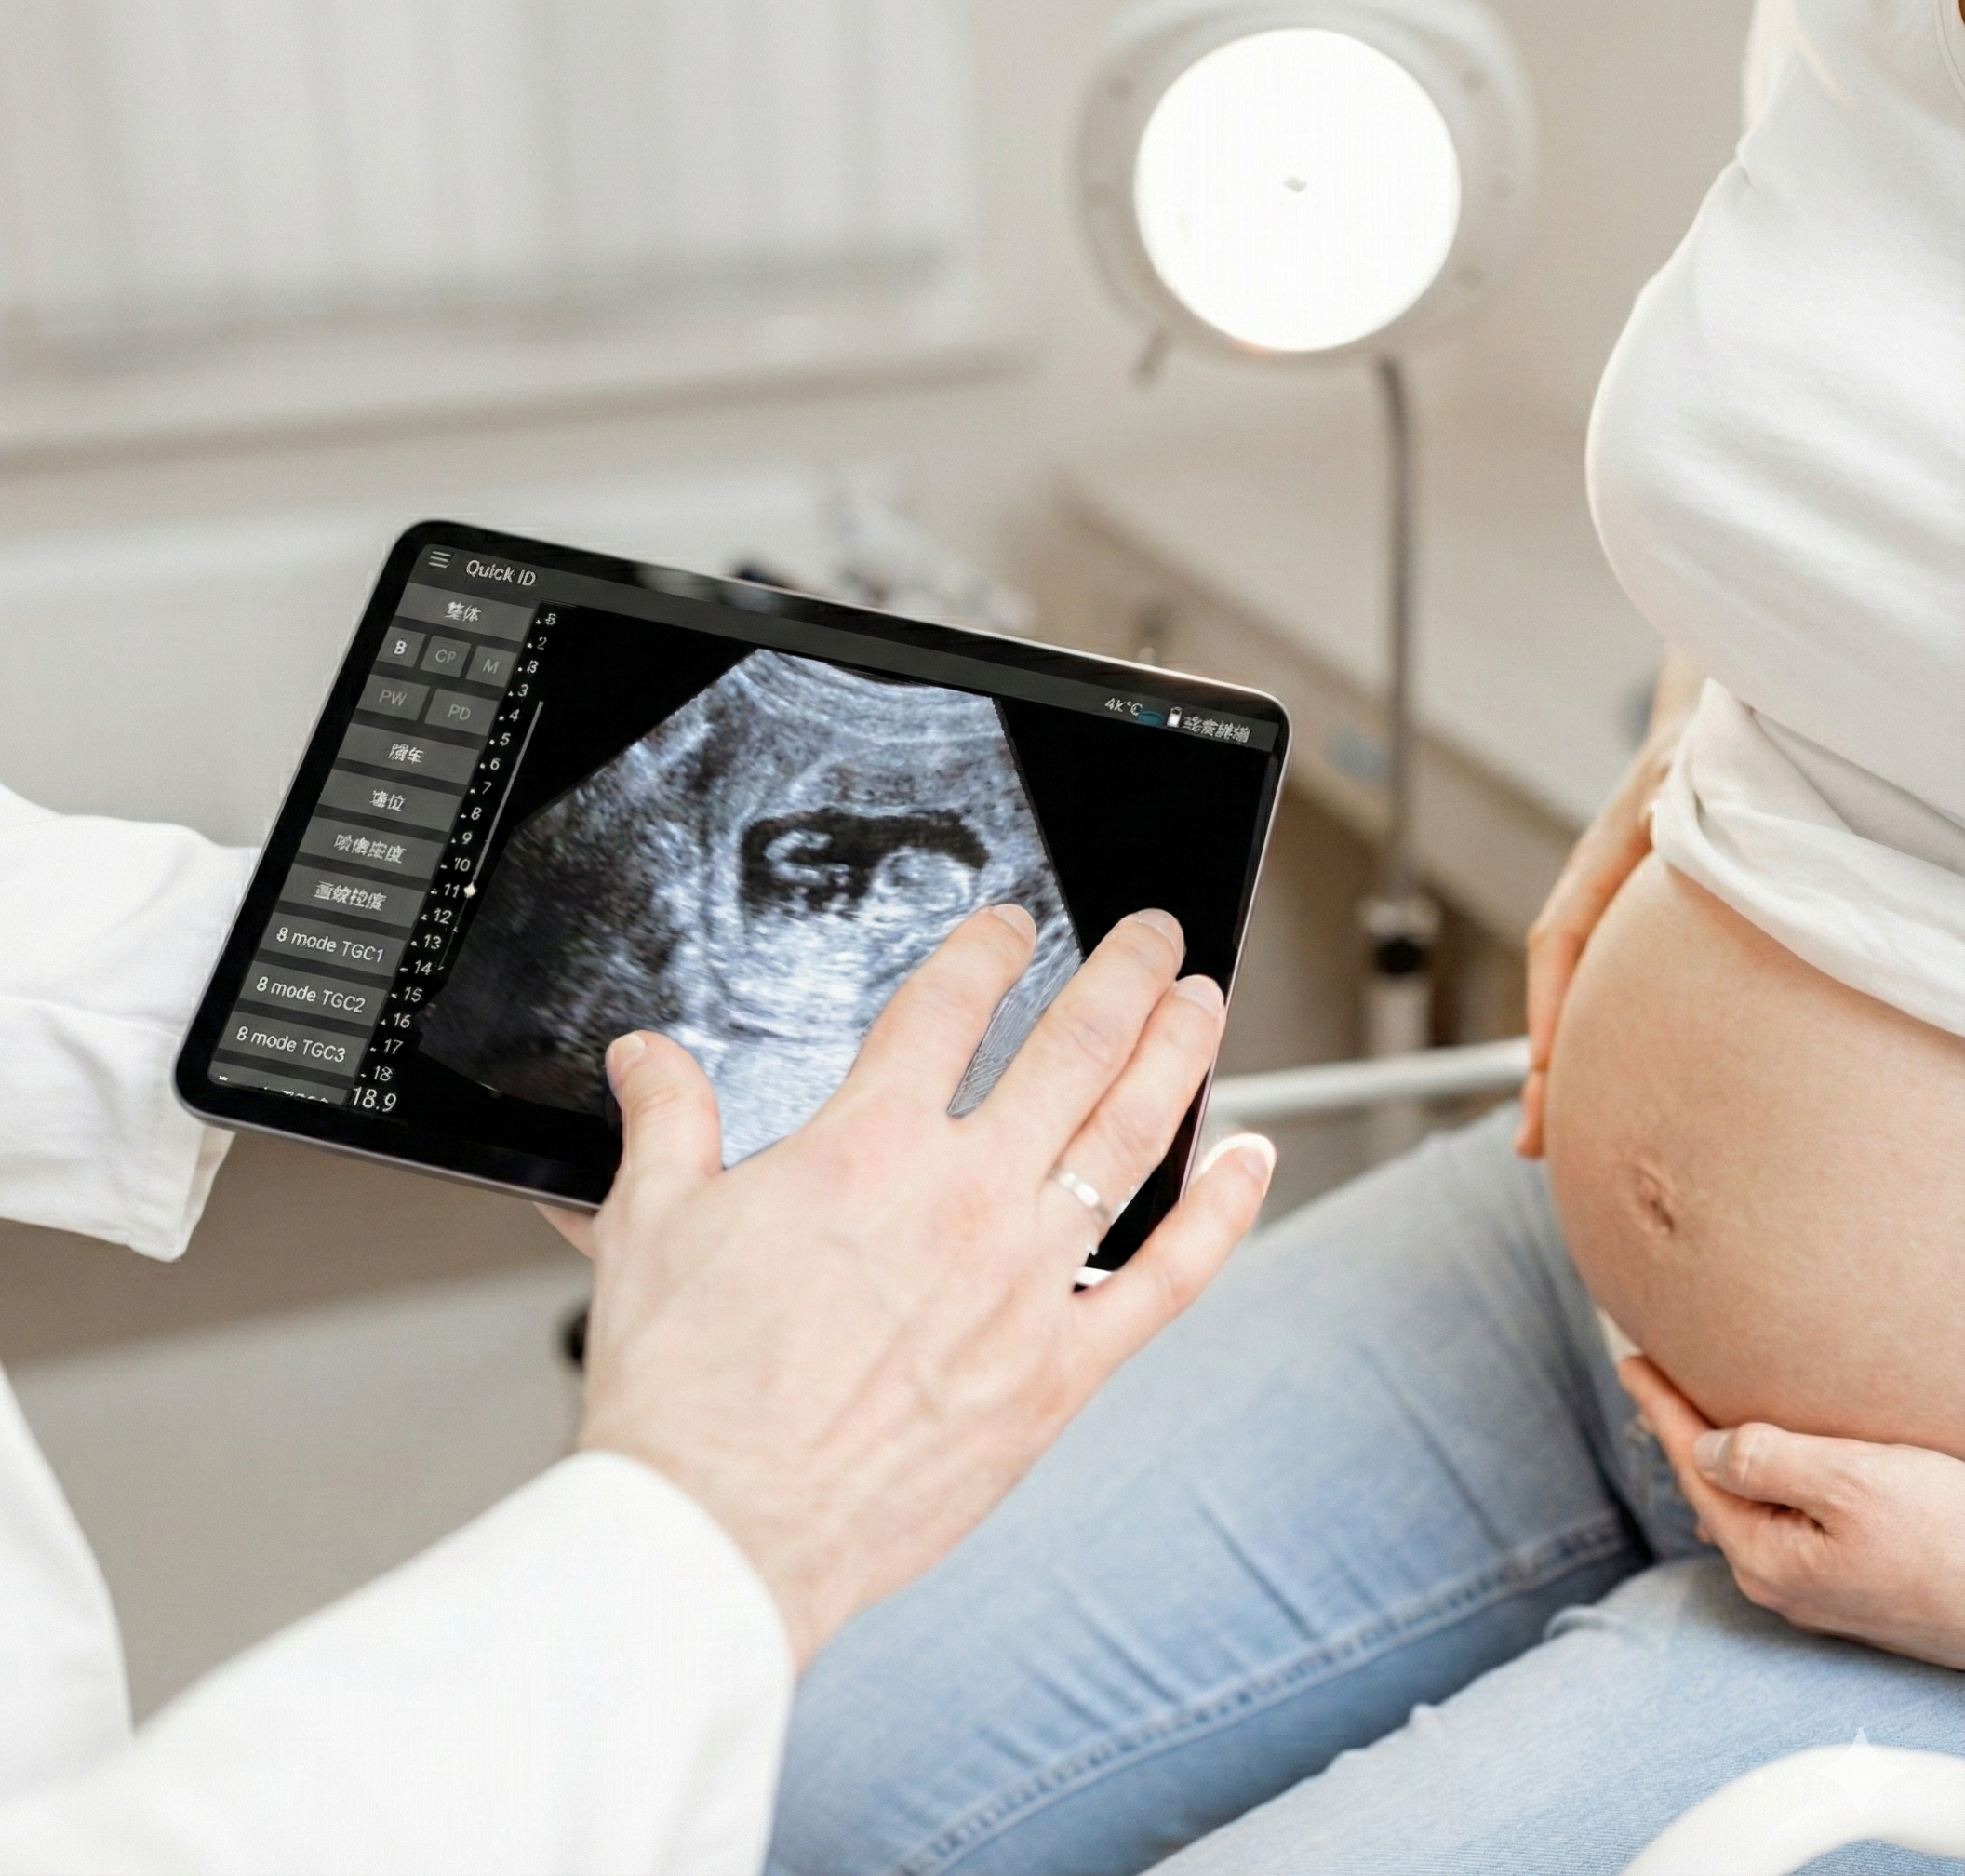

AI-Powered Remote Ultrasound for Cardiology & OB/GYN

Bringing real-time AI scanning support and expert remote diagnostics together — closing the gap in access and accuracy of care.

Built from a dataset of millions de-identified ultrasound images, our AI models cover Obstetrics, Cardiology, and Gynecology. They analyze key anatomical structures in real time, providing accurate biometric measurements and insights that help clinicians assess fetal growth, cardiac function, and organ health with greater speed and confidence.

Healium Sono combines real-time AI-guided ultrasound scanning with expert remote diagnostics to deliver fast, accurate, and accessible care. Our platform bridges the gap between limited on-site expertise and high-quality imaging, empowering clinicians to perform confident cardiac and OB/GYN assessments wherever care is needed.